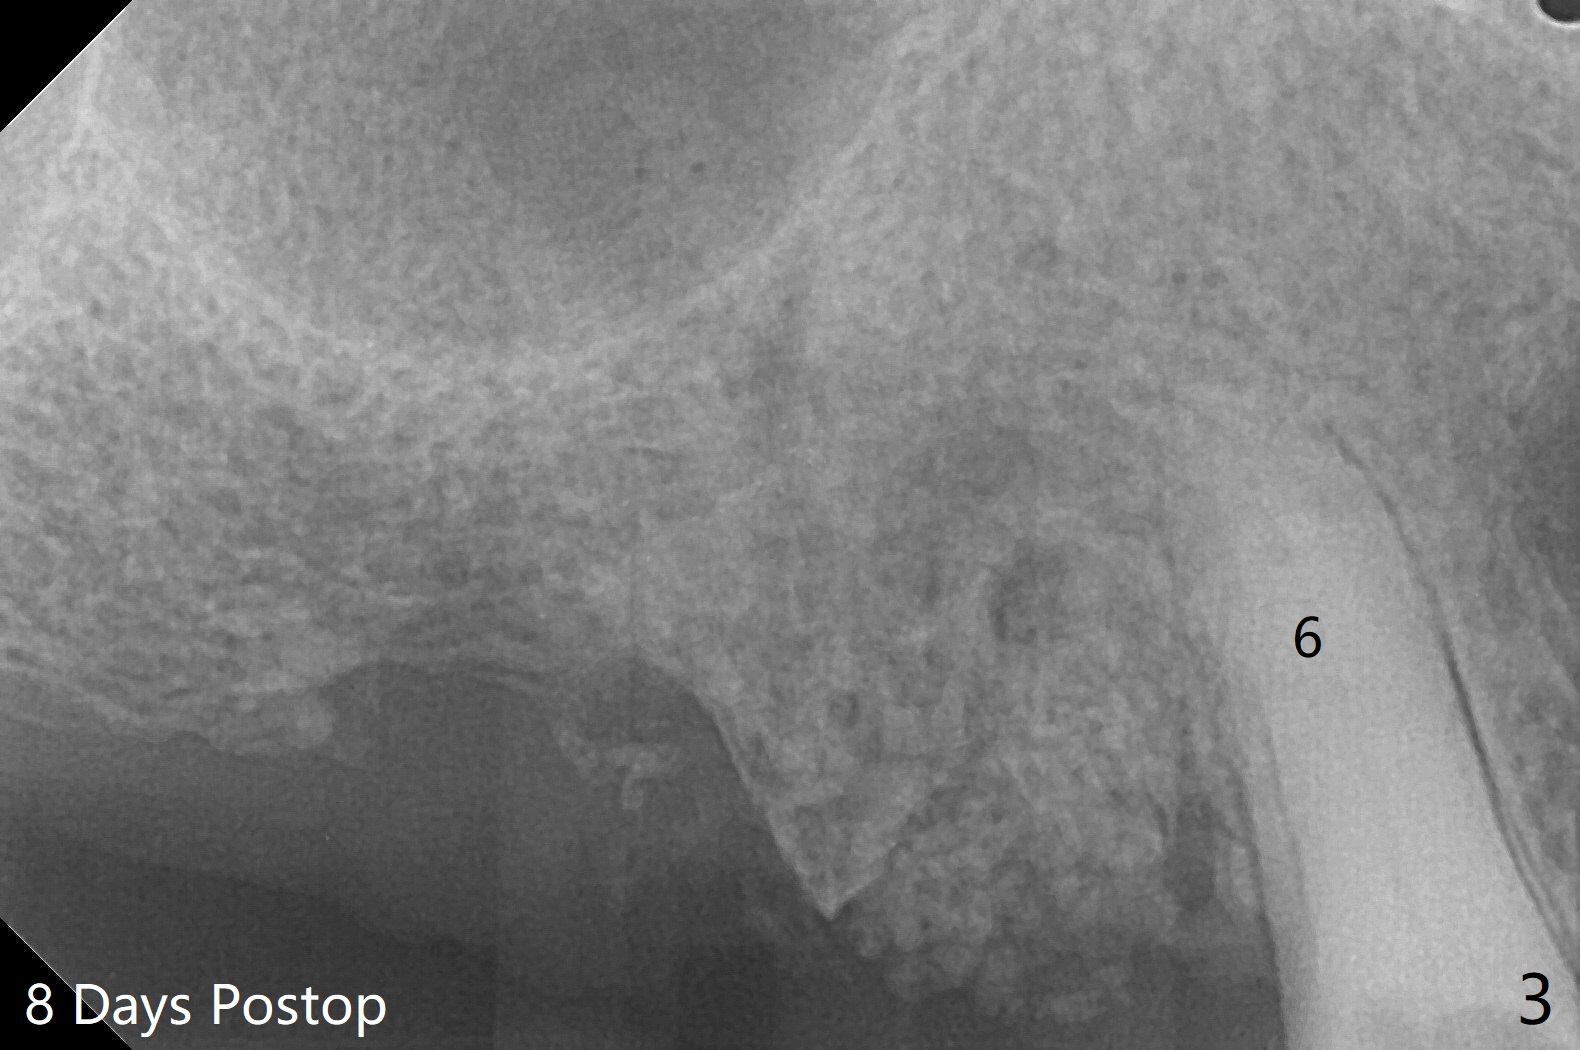

A 84-year-old man has upper right discomfort. Exam shows #4,5 residual roots have percussion pain, while the apex of #4 is buccally exposed (Fig.1). After extraction of #4 and 5 and debridement, collagen plug is inserted to the buccal defect. Then cortical allograft is placed in the sockets and covered with 8x8 mm BioXclude. The wound is approximated with 4-0 PGA suture. With use of BioXclude, the bone graft appears to remain in place 8 days postop (Fig.2,3). The apical perforation at #4 seems to be healing (Fig.2 >).